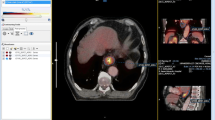

Thirty-nine patients were prospectively recruited for this study. In 2 patients, there was technical failure during 4D reconstruction, resulting in a total of 37 patients available for analysis. The patient characteristics are shown in Table 1. Based on all staging procedures combined, most patients had a clinically node-positive adenocarcinoma located in the distal oesophagus or gastroesophageal junction. Figure 1 shows images of a patient with a node-positive gastroesophageal junction tumour. After staging, patients were treated with neoadjuvant chemoradiotherapy (n = 23), definitive chemoradiotherapy (n = 9), neoadjuvant chemotherapy (n = 1) or palliative treatment (n = 4).

Motion-compensated (MC) and three-dimensional (3D) positron-emission tomography/computed tomography (PET/CT) of a patient with a gastroesophageal junction tumour. Fused PET/CT (a,d,g,j) and PET only (b,e,h,k) transversal slices, and maximum intensity projection (c,f,i,l) images of the primary tumour are shown in the upper panels (a–f), and a highly suspicious lymph node at the celiac trunk is shown in the lower panels (g–l). The primary tumour showed a maximum standardized uptake value (SUVmax) of 12.0 on 3D PET/CT and 14.7 on MC PET/CT. The pathological lymph node showed a SUVmax of 6.6 on 3D PET/CT versus 7.6 on MC PET/CT